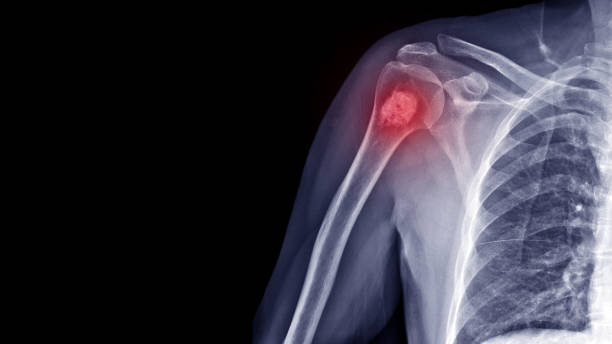

골육종은 일반적으로 무릎 근처의 경골, 무릎 근처의 대퇴골 또는 어깨 근처의 상완골에서 발생하는 뼈의 암입니다. 소아에서 가장 흔한 유형의 뼈 암입니다.

그리고 일반적으로 골육종 진단을 위해 사용되는 검사로는, 엑스레이 검사, CT 검사, MRI 검사 등이 있습니다. 엑스레이 검사는 뼈를 포함하여 신체 내부의 조밀한 조직의 이미지를 생성합니다. CT 검사는 신체의 뼈와 연부 장기를 검사하는 데 사용되는 3D 검사입니다. MRI검사는 음파와 강력한 자석을 사용하여 내부 장기의 이미지를 생성합니다. 뼈스캔 검사는 다른 영상 도구로 놓칠 수 있는 뼈 이상을 보여주는 민감한 영상 검사입니다. 뼈 스캔은 또한 암이 다른 뼈로 퍼졌는지 여부를 알 수 있습니다. 가장 먼저 실시되는 검사는 일반적으로 X-ray검사입니다.